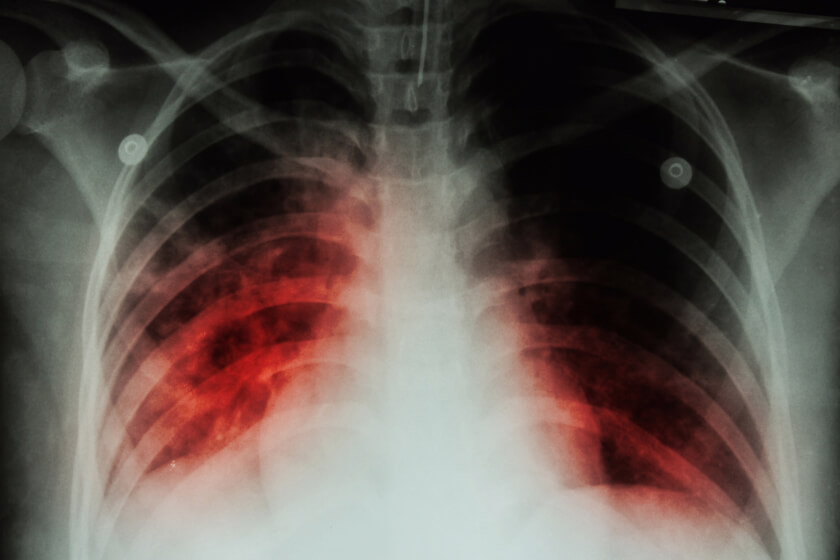

COPD also narrows airways. Chronic obstructive pulmonary disease is an umbrella term that covers two respiratory diseases: emphysema and chronic bronchitis. Emphysema causes the walls of the alveoli to become inflamed and lose elasticity, which eventually causes the bronchioles to collapse. Chronic bronchitis is long-lasting inflammation of the bronchial tubes, which causes severe coughing spells that bring up mucus, wheezing, shortness of breath, and chest pain. Chronic inflammation can also cause thickening and scarring of the bronchial tubes.

Cigarette smoking can also narrow lung airways. Chemicals in the smoke irritates the tender tissue in the bronchioles; smoking for years can cause chronic inflammation and thickening of the walls of the air sacs. The damage to alveoli cannot be reversed, and can lead to the development of COPD. The inflammation can also decrease the size of the empty space within the trachea, known as the lumen, to reduce air flow into the lungs.

Using the results of the CT scans, the researchers assessed each participant’s airway disease by measuring several metrics, including airway wall thickness and the diameter of the lumen. The researchers found that, of the 9,363 smokers in the study, men had thicker airway walls while women had a narrower lumen diameter. They also found that the women who had thicker airway walls or a narrower lumen diameter had poorer lung function, more shortness of breath, and worse overall survival. The female smokers also had a higher risk for mortality than did their male counterparts.

The research underscores the importance of considering gender when it comes to assessing patients’ risk for COPD and breathing problems associated with respiratory disease. CT scan can help detect signs of COPD, such as bronchial wall thickening, which can lead to early detection and treatment that slows the progression of COPD.